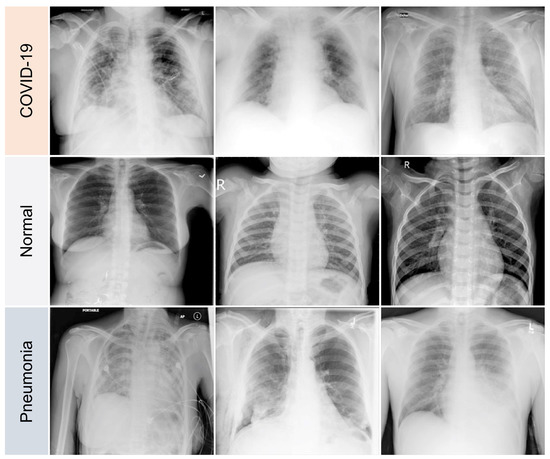

4.1. Data Processing

- GGOs.

- Odd paving pattern.

- Consolidation of the airspace.

- Thickening of bronchovascular bundles.

- Traction bronchiectasis.

- Reticular opacities.

- Vascular thickness.

- Additional widespread distribution along the bronchovascular bundles.

- Thickness in bronchial wall.